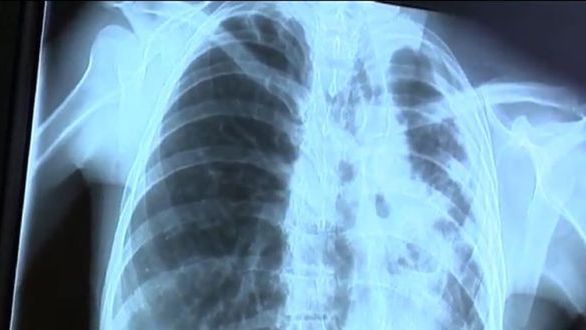

Zbigniew S. od kilku lat choruje na gruźlicę. Chociaż rodzina oraz pracownicy sanepidu wielokrotnie próbowali nakłonić 54-letniego mężczyznę do podjęcia leczenia, ten twierdzi, że niekonwencjonalne metody mu wystarczą. Wielokrotnie bywał w szpitalach, jednak za każdym razem został wypisywany na własne życzenie.

W marcu 2014 roku za narażenie życia innych 54-latek został skazany na 10 miesięcy więzienia. Kara została zawieszona na trzy lata. W tym czasie mężczyzna miał podjąć leczenie. Jednak dotychczas nie zgłosił się do szpitala. Wczoraj wrocławski sąd skazał mężczyznę na karę 10 miesięcy więzienia, ponieważ ten nie chce się poddać leczeniu. Za kratkami będzie musiał poddać się leczeniu.